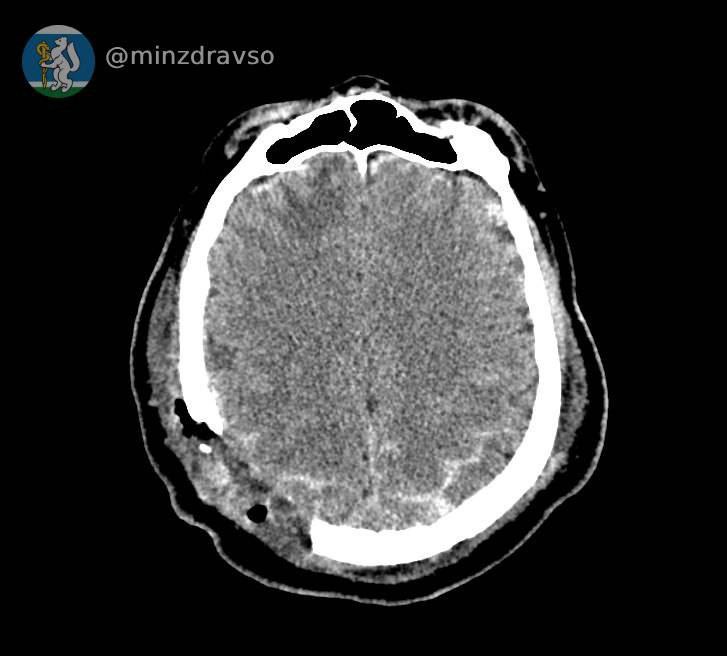

У 57-летнего свердловчанина раскололся череп

Его ударила стрела крана

Житель Серова получил удар стрелой строительного крана. У него раскололся череп. В критическом состоянии свердловчанин поступил в Серовскую городскую больницу. Реаниматологи смогли стабилизировать состояние пострадавшего. Врачи провели телеконсультацию с экспертами из Екатеринбурга. Они подтвердили, что нужна перегоспитализация в ближайший межмуниципальный медцентр. Мужчину срочно привезли в Городскую больницу № 1 Нижнего Тагила. Там его приняла бригада медиков и провела операцию. Врачи извлекли обломки костей и убрали гематомы. Кроме того, была восстановлена целостность твердой мозговой оболочки.

«После завершения лечения пострадавшего выписали из стационара. У него восстанавливается речь, к пострадавшим конечностям возвращается подвижность», — информирует минздрав.

Фото: минздрав Свердловской области